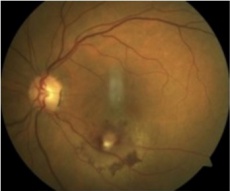

Choroidal melanoma fundus photo and B scan. This tumor was initially treated as choroidal hemangioma. [30] |